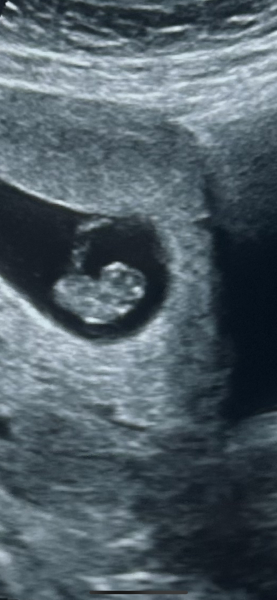

I had my scan today. They measured me a day further than I thought I would be and put me at 5+5. They saw the yolk sac and fetal pole but said it was too early to see the heartbeat at this stage. You can't see that until after 6 weeks so I have to go back for a rescan in a few weeks

Thank you! Just had it now. All good and one strong heartbeat 😀

Congratulations! Such a cute little blob!

@Lemonbalm8 I don't know if she measured the heartbeat but she said it was fast and strong. She measured me at 6+6. Fingers crossed for yours 😀

Don't worry! Glad the scan was okay ☺️. I actually had another scan this morning. Measuring 8+2 and had my booking apt last week x